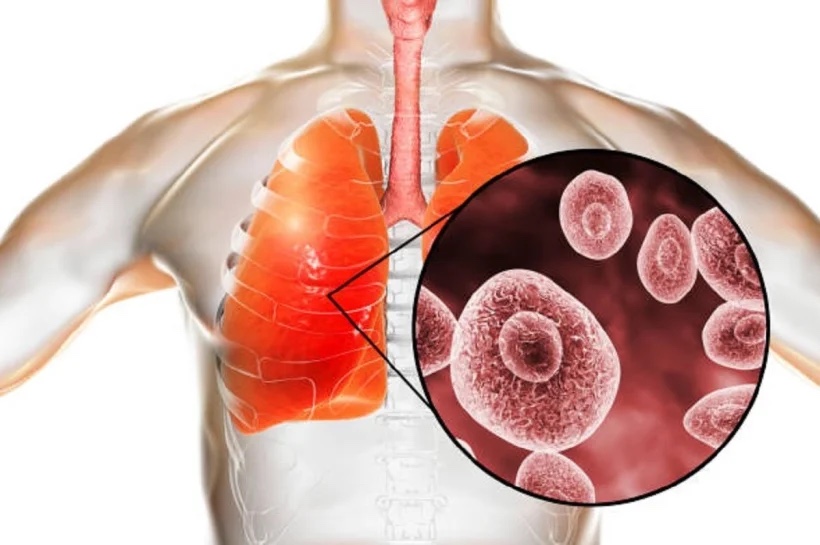

क्या है म्यूकरमाइकोसिस– म्यूकरमाइकोसिस एक ऐसा फंगल इंफेक्शन है जिसे कोरोना वायरस ट्रिगर करता है. कोविड-19 टास्क फोर्स के एक्सपर्ट्स का कहना है कि ये उन लोगों में आसानी से फैल जाता है जो पहले से किसी ना किसी बीमारी से जूझ रहे हैं और जिनका इम्यून सिस्टम कमजोर होता है. इन लोगों में इंफेक्शन से लड़ने की क्षमता कम होती है.

कैसे बनाता है शिकार– एक्सपर्ट्स के मुताबिक, हवा में फैले रोगाणुओं के संपर्क में आने से कोई व्यक्ति फंगल इंफेक्शन का शिकार हो सकता है. ब्लैक फंगस मरीज की स्किन पर भी विकसित हो सकता है. स्किन पर चोट, रगड़ या जले हुए हिस्सों से ये शरीर में दाखिल हो सकता है.